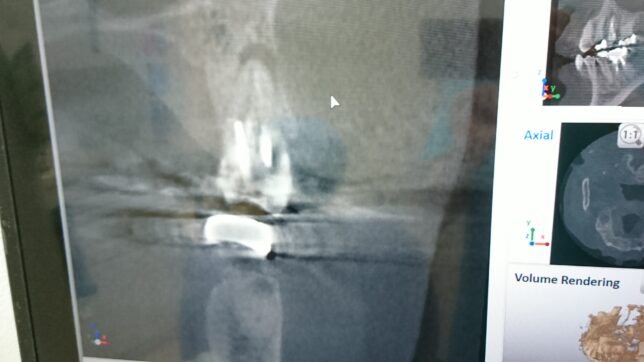

その3 根の病気になって悪化すると抜歯に至ることがある。

歯の神経を抜いても神経が入っていた管に菌が残ってしまうことがあり、

それが歯の根の外に出ると、顎の骨を溶かして病巣が出来ることがあります。

根尖性歯周炎といいます。この病巣が大きくなると、歯の根の治療では治りにくくなり、抜歯に至ることがあります。